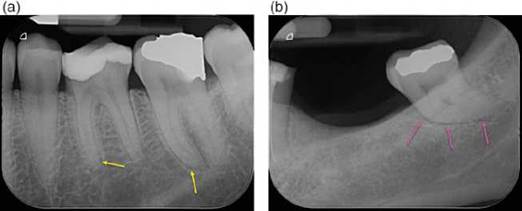

Figure 6.8 Periodontal ligament space. (a) Periapical radiograph of the mandibular right first, second and third molars. The predominantly horizontally oriented boney trabeculae (yellow arrows). Wider marrow spaces (blue arrow) may be mistaken for periapical radiolucencies. (b) The trabeculae in the maxilla (pink arrows) are thinner and more compact compared to those in the mandible.

The dense, outer cortical bones of the jaws and facial skeleton form a protective layer and encase the enclosed cancellous bone. Cancellous bone is a light porous bone, arranged into a matrix of interspersing bony projections from the cortex of bone spicules called trabeculae (Figure 6.8). The spaces between trabeculae contain vasculature and bone marrow. The arrangement of the tra- beculae gives rise to the typical granular appearance of the bone of the alveolar process surrounding the roots of teeth on radio- graphs. The trabeculae tend to be thicker and horizontally striated in the mandible and the marrow spaces tend to be wider. In the max- illa the trabeculae tend to be thinner and more compact than in the mandible, resulting in typically smaller marrow spaces. However, there is significant inter-individual variation and the organization of the trabeculae, and therefore the radiographic appearance of the trabeculae and marrow cavities at any given site is related to functional stress on the teeth supported by the bone at that site [15, 47, 50].

Conventional radiography: The true definition of the trabeculae and marrow spaces of cancellous bone on periapical radiographs is obscured by the anatomical noise created by the overlying cortical plate, as well as by the compression of adjacent anatomical structures on to the 2-dimensional radiograph. As such, the subtle changes in the organization of the cancellous bone often associated with the development of AP are difficult to identify. On occasion, to the inexperienced clinician, a well-defined, larger marrow space superimposed over a root apex may be misinterpreted as a AP.